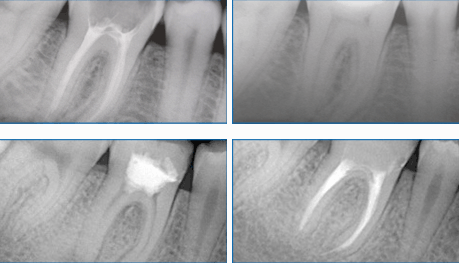

Если кариозный процесс зашел так далеко, что затронул уже сосудисто-нервый пучок зуба (так называемый «нерв»), необходимо эндодонтическое лечение: удаление пресловутого «нерва» и последующее пломбирование корневых каналов. И здесь решающим фактором, определяющим успех лечения, является качественное пломбирование корневых каналов.

До и после лечения, протезирования